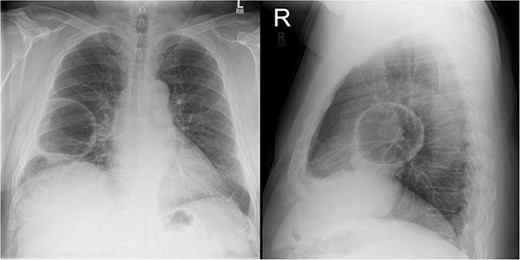

On examination, he appeared well, with no oxygen requirement and reduced air entry in the right mid to lower chest. A chest X-ray (Fig. 1) showed a large cavitating lesion in the right lower zone with a chest computed tomography (CT; Fig. 2) confirming a large lung lesion measuring 100 mm × 80 mm × 100 mm with surrounding ground glass changes. Tests for SARS-CoV-2 and hydatid serology returned positive. He proceeded to have a bronchoscopy and bronchoalveolar lavage that was negative for aspergillus, galactomannan, mycobacterial and fungal cultures, cryptococcus, respiratory viral panel and cytology. A CT abdomen (Fig. 3) revealed multiple hepatic cysts with the largest measuring 59 mm in size in the right lobe. Given the findings of lung and liver lesions, he was commenced on albendazole for presumed extra-hepatic hydatid disease and referred to the cardiothoracic team for resection of the pulmonary hydatid cyst.